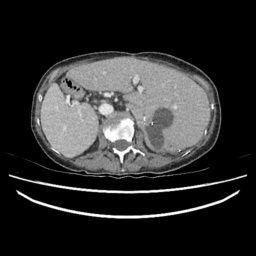

(e) Normal Liver

Refer to caption

(f) Normal Liver

(g) Liver Tumor

(h) Liver Tumor

Figure 4: We show some example brain MRI slices from BratS18 (first row) and Liver CT slices from LiTS (second row). Both normal- and abnormal-looking images are provided.

LiTS.

We also experiment with the LiTS data containing a total of 131 contrast enhanced abdominal CT volume images of the liver acquired from 7 different clinical institutions. The in-plane resolution ranges from 0.5mm to 1mm and the slice thickness ranges from 0.7mm to 5.0mm. Each slice is 512×512512512512\times 512 in size and we resize them to 256×256256256256\times 256, and as with the BratS18 MRI not every slice contains a lesion and so these slices are considered to be healthy images. A detailed data description can be found on the challenge website. 222https://competitions.codalab.org/competitions/17094

Aside from the difference in imaging tissue and modality of these two data sets, the tumor regions on the CT images are of different shape and size, as can be seen in Figure 4. Also, many CT scans are acquired in a way that introduces greater noise-like artifacts than MRI. For each dataset, 80%percent8080\% of randomly selected data are used for training and the resting 20%percent2020\% for testing.

IV-E Results on the LiTS Challenge dataset.

We also implement ANT-GAN on the LiTS dataset and show some qualitative results in Figure 11. We observe that the lesions in the liver CT data appears with much lower contrast than in the brain MRI data. While our model can detect and modify the abnormal regions successfully, we note that there are more deformations than with the BratS18 dataset, which is a result of this more difficult task.